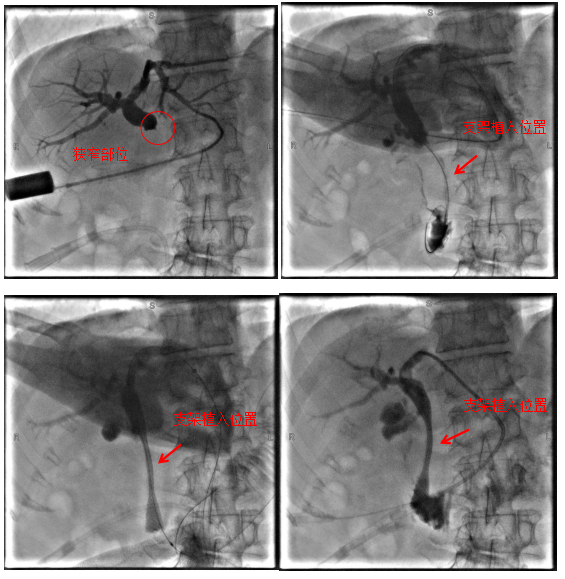

病例1

69歲老年患者,因“中上腹疼痛1周”于我院肝膽胰外科住院治療,完善相關檢查后考慮診斷為:胰腺惡性腫瘤、梗阻性黃疸等,因腫瘤分期晚并出現遠處轉移,已無根治性手術指征,且因腫瘤侵犯十二指腸導致腸腔狹窄,無法實施ERCP+膽道支架植入術解除膽道梗阻,經過科室團隊充分評估,決定為患者行經皮經肝膽道支架植入術,手術順利,術后患者黃疸逐漸消退,為后續治療提供了堅實的保障。

術中影像